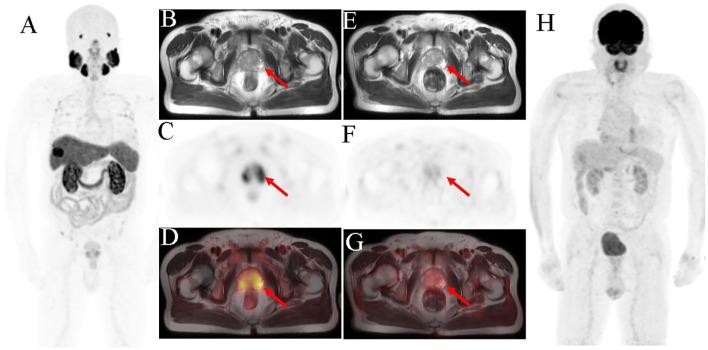

Radionuclide probes-targeted prostate-specific membrane antigen (PSMA) is used in diagnosis and treatment of prostate cancer (PCa). Recent studies have shown that PSMA is expressed in the tumor neovascular endothelium, such as in malignant liver tumors. We report a case of PCa with incidental intrahepatic cholangiocarcinoma (ICC) detection using F-PSMA-1007 and F-fluorodeoxyglucose (FDG) positron emission topography (PET)/MRI.F-PSMA-1007 PET/MRI of our patient with PCa showed that one liver lesion had high PSMA uptake. F-FDG PET/MRI revealed minimal FDG uptake in the liver lesion. Histopathological examination revealed that the liver lesion was moderately to poorly differentiated cholangiocarcinoma. Our studies, along with others, demonstrated that malignant liver tumors, such as ICC, hepatocellular carcinoma (HCC), and combined hepatocellular-cholangiocarcinoma (CHC), and benign lesions, such as benign liver hemangioma, focal nodular hyperplasia, focal inflammation and steatosis, vascular malformation, and fatty sparing, exhibited elevated PSMA uptake. Moreover, PSMA-PET was superior to FDG-PET in detecting ICC and HCC, indicating that PSMA-PET may be used as alternative staging and to identify patients for PSMA-targeted therapy.

摘要